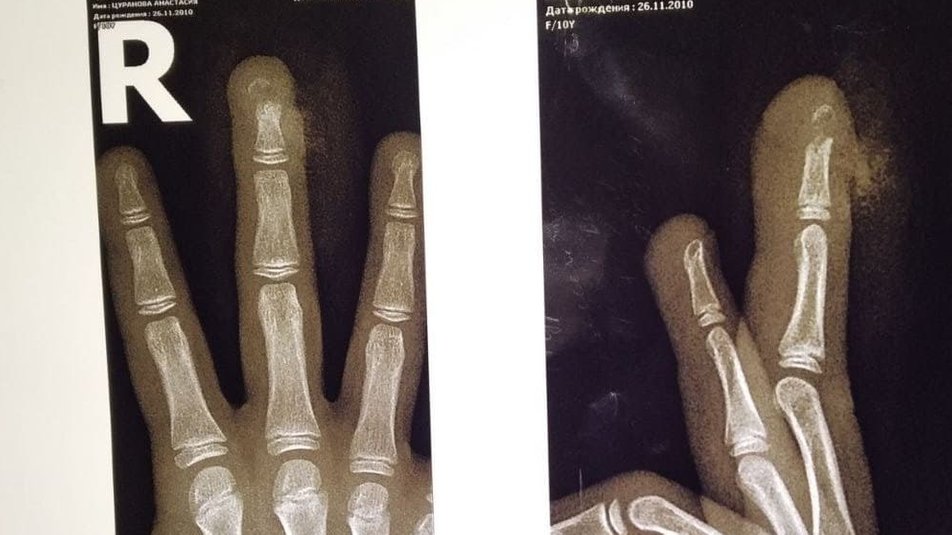

Марина Цуранова требует возмещения за лечение дочери: девочке школьными дверями зажало пальцы. Женщина говорит, что учителя не вызвали скорую. В больницу ребенка она везла самостоятельно, медики диагностировали перелом.

10-летняя ученица харьковской школы №54 — утром в кабинете врача, сообщает "Суспільне". У девочки — открытый перелом среднего пальца, ей провели операцию. Каждые два дня Настя ездит на перевязки.

"Три с половиной или четыре недели будет перелом срастаться. Рана будет заживать недели две", — говорит врач детского травматологического отделения Сергей Филиппов.